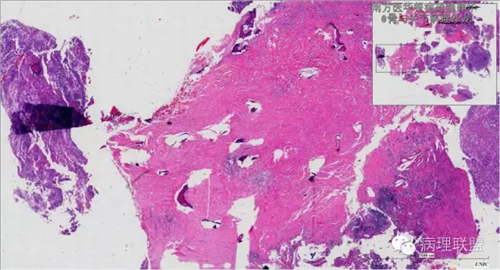

来源于组织细胞的相似性骨病ECD vs RDD 看图说话

病例由南方医华银病理魏建华提供,致谢。